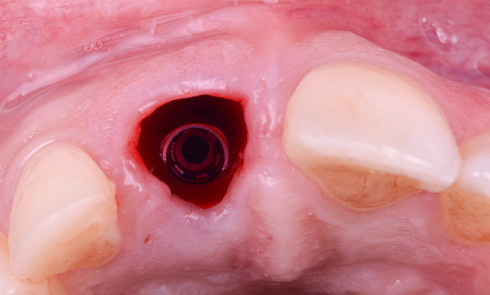

RÉSUMÉ Cet article présente un cas clinique illustrant une technique d’extraction-implantation immédiate à l’aide d’un pilier SSA. Il présente les défis de...

Remaniements tissulaires post-extractionnels L’extraction d’une dent déclenche une série de modifications des tissus environnants [1]. Il existe un affaissement du...